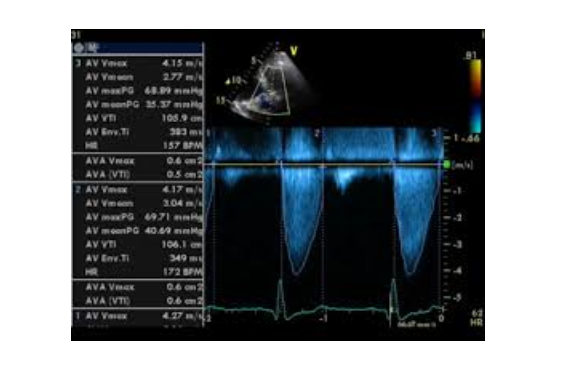

4. Siêu âm Doppler tim

Khi chùm tia siêu âm đi qua 1 vật thể chuyển động sẽ sinh ra hiệu ứng Doppler. Hiệu ứng Doppler là đại lượng phản ánh vận tốc của vật thể chuyển động được thu nhận, xử lý và biểu hiện qua dạng âm thanh, dạng sóng hoặc mã hóa thành màu. Trong siêu âm Doppler tim, hiệu ứng Doppler phản ánh vận tốc chuyển động của dòng máu và của cơ tim. Dòng máu đi qua chỗ hẹp có vận tốc lớn, khi đó tín hiệu âm thanh sẽ có âm lượng lớn và âm sắc cao, tín hiệu dạng sóng sẽ có biên độ lớn. Với Doppler mầu, dòng máu được mã hóa thành mầu đỏ nếu đi về phía đầu dò và thành mầu xanh khi đi xa đầu dò, theo đó sẽ phát hiện được các dòng máu bất thường trong tim. Nói một cách ngắn gọn, siêu âm Doppler tim là phương tiện rất hữu hiệu trong đánh giá huyết động qua các van tim, phát hiện các dòng máu bất thường trong tim và tình trạng vận động của cơ tim.